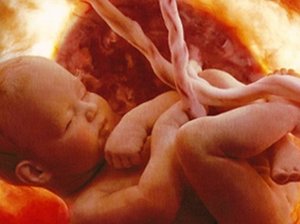

Обвитие пуповиной вокруг шеи плода — распространенное явление, которое наблюдается у многих беременных женщин. Врачи отмечают, что в большинстве случаев это не представляет серьезной угрозы для здоровья ребенка. Пуповина может обвиваться вокруг шеи как один, так и несколько раз, но важно понимать, что она обладает определенной эластичностью и может позволять плоду свободно двигаться.

Тем не менее, в некоторых случаях обвитие может привести к осложнениям, таким как гипоксия или затрудненные роды. Поэтому врачи рекомендуют проводить регулярные ультразвуковые исследования для мониторинга состояния плода и пуповины. Если обвитие фиксируется, специалисты могут предложить дополнительные методы наблюдения и, при необходимости, планировать роды с учетом возможных рисков. Важно, чтобы будущие мамы не паниковали и доверяли своему врачу, который сможет дать квалифицированные рекомендации и обеспечить безопасность как матери, так и ребенку.